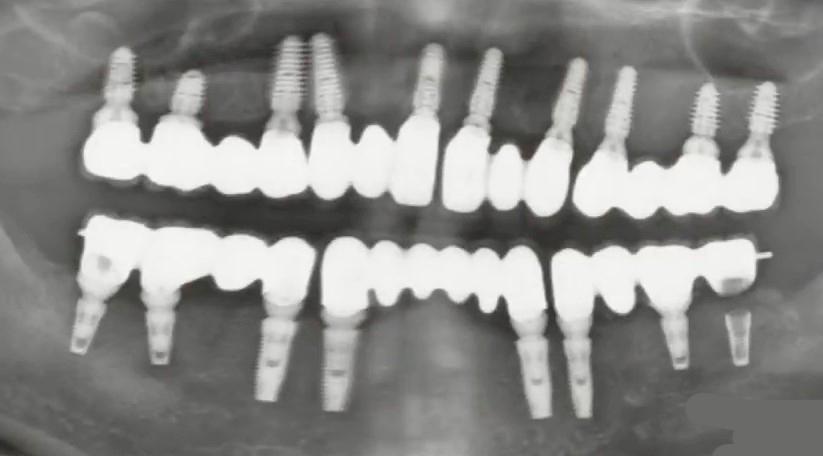

The images below show the implants placed according to the above-mentioned scheme. In the upper jaw, 10 cancellous implants were placed, 8 of which are used to support the temporary prosthesis. The 2 distal implants were placed with insufficient torque and were not loaded. In the lower jaw, 8 implants were placed, 6 of which are used to support the temporary prosthesis for the same reason.

Orthopantomogram of successful placement of cancellous (upper jaw) and cortical (lower jaw) implants. YouTube / Dr. Kamil Khabiev / Dental Guru Academy